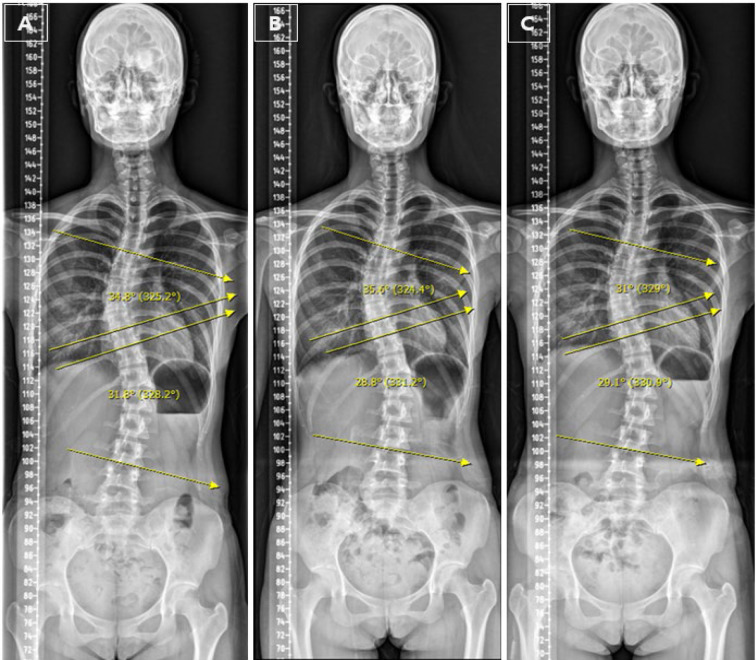

[Purpose] This case study explored the potential of Spontaneous Movement Therapy (SMT)-an active-modified form of Vojta therapy-in improving spinal alignment parameters in a young adult with a history of Adolescent Idiopathic Scoliosis (AIS). [Participant and Methods] A 21-year-old female with a prior diagnosis of AIS was assessed using full-spine radiographs, which revealed thoracic dextroscoliosis (35.6°) and lumbar levoscoliosis (28.8°). She reported no spinal pain or leg length discrepancy. The patient subsequently underwent an 8-week SMT intervention targeting both coronal and sagittal spinal alignment. [Results] Following the SMT intervention, the thoracic Cobb angle decreased by 4.6° (from 35.6° to 31°), and the angle of trunk rotation (ATR) decreased by 4.0° in the thoracic spine and 3.33° in the lumbar spine. The lumbar Cobb angle remained largely unchanged (28.8° to 29.1°). Although the Cobb angle and ATR were reduced, these changes did not exceed the minimal clinically important difference (MCID). [Conclusion] Although this case report presents promising preliminary observations, the reductions in spinal curvature parameters did not exceed the MCID, suggesting the need for cautious interpretation. Further studies with larger sample sizes and control groups are warranted to validate the clinical effectiveness of SMT in AIS management.